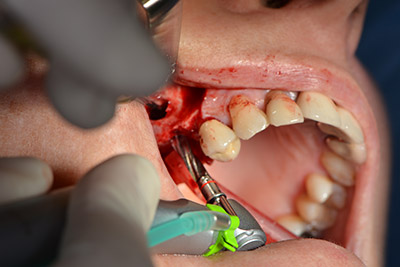

The following holes were drilled at a reduced speed of 300 rpm. The Implantmed demonstrated its true capability at this stage. The surgical protocol can be preset – the various positions can be selected simply by pressing the “P” position of the foot control (Fig. 10 to 11).